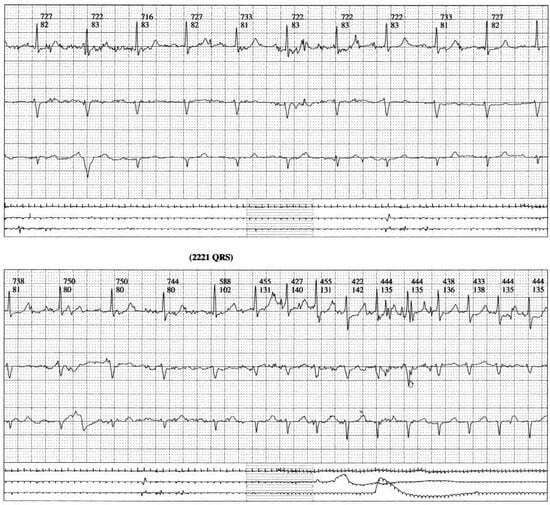

Figure 1a.

Dynamic ECG recording during jogging. Beginning of the tachycardic arrhythmia. Symptomatic long run long lasting tachyarrhythmia (2221 QRS complexes). Begining of atrial ectopic beats of undetermined origin (probably automatic aetiology). Heart rate up to 170/min.

Figure 1b.

Dynamic ECG recording during jogging. Change from atrial arrhythmia to paroxysmal atrial fibrillation.